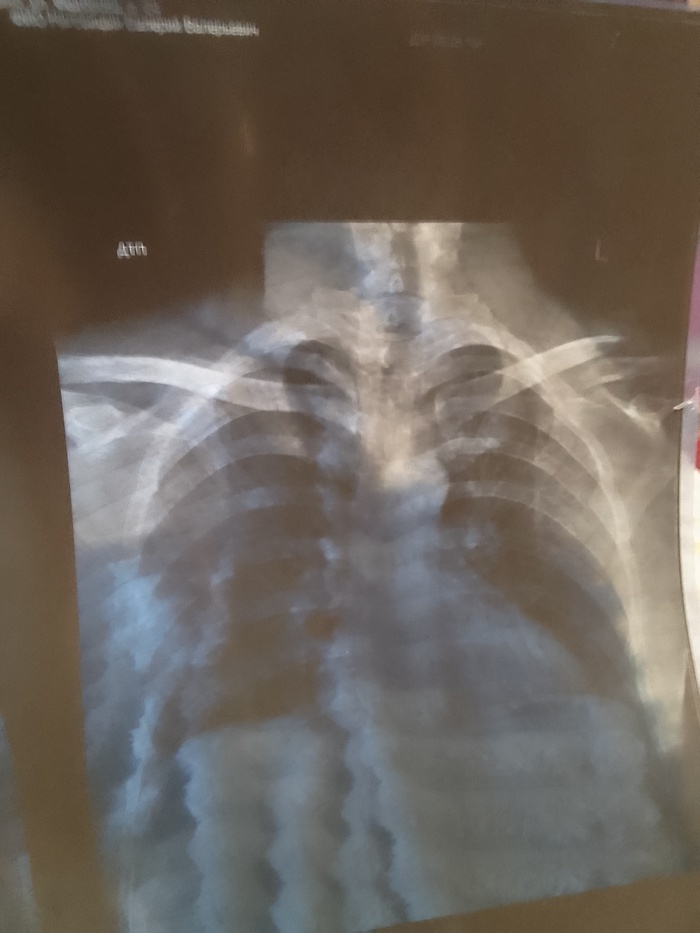

Всем привет. В общем и целом попал в дтп 24.09. (Мой апм совет не ездить на попутках). Собрали 4 встречных автомобиля,в 5-ю прилетел аккумулятор от нас.и разбил лобовое. Удар был в левый борт. Спасатели спилили крышу чтобы нас вытащить. Был за водителем слева. Сломано: шея, ключица, 3 ребра. Сотрясение мозга. 4 ушиба спинного мозга(позвоночника). Сидел я На пассажирском сиденье.был пристегнут. После аварии сделали 2 операции. 1. Вставили титановый межпозвонковый диск. 2 поставили плиту на левую ключицу из медицинской стали. Первую операцию делали через разрез на шее.по этому 1 месяц ел только детские пюре. Интервал между операциями 6 дней. Врачи сказали что Во время столкновения когда сломало шею, задело артерию. И кровью залило левое полушарие. В итоге была амнезия.сейчас все норм. Восстановился. Когла я окреп и воосстановился через 7 месяцев после дтп. Жена ушла от меня. Через 9 месяцев мы официально развелись по обоюдному согласию . С ней мы прожили без 3-х месяцев 10 лет. После развода. Прожили еще 10 дней. Она дала мне второй шанс. Но я неисправим. В итоге мы разошлись навсегда.живем сейчас по разным городам . Расстояние 3500 километров. Жизнь продолжается в новом ключе. У меня новая работа. Новая жизнь. Теперь живу один. Берегите себя и свою жизнь и цените то , что имеете. здоровье восстановилось все, кроме мозга. Алкоголь теперь под запретом. От слова совсем. Один раз попробовал . На утро 40 минут пытался вспомнить . Кто я и где я. Всем удачи в этой жизни и никогда не расстраивайтесь по пустякам. Я выжил. И я благодарен врачам за то что спасли. И жене(теперь уже бывшей) что выходила меня после аварии.